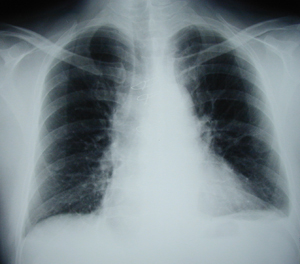

Εικόνα 1

Απλή οπισθιο-πρόσθια ακτινογραφία θώρακος που δείχνει ευμεγέθη μάζα στο οπίσθιο μεσοθωράκιο. Η ακτινογραφία ανήκει σε θήλυ ασθενή ηλικίας 30 ετών χωρίς συμπτώματα.